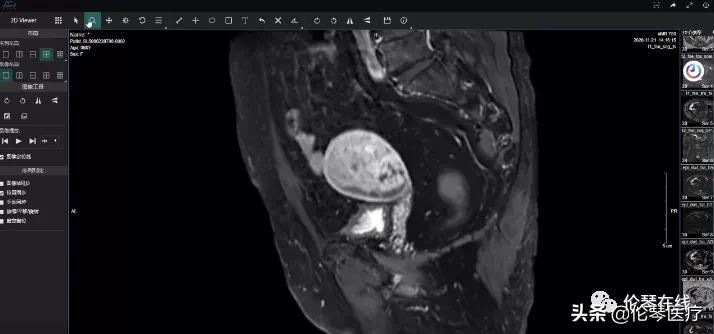

今天伦琴医疗和大家分享腹部子宫占位的鉴别诊断病例。

病例分析视频截图如下

上期病例答案公布——子宫癌肉瘤